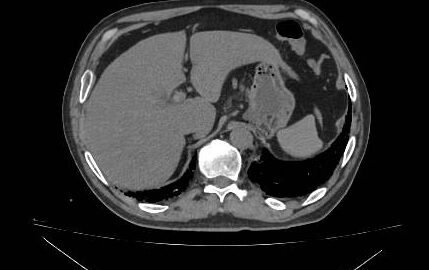

En caso de obtener resultados compatibles con enteropatia perdedora de proteínas planteo estudio mediante enteroTAC o endocapsula, sospechando enfermedad de int delgado como por ej linfangiectasia